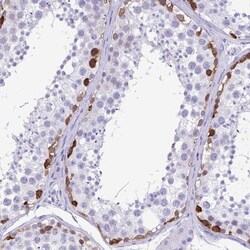

- Immunohistochemical staining of TSPY10 in human testis using a TSPY10 Polyclonal Antibody (Product # PA5-61949) shows strong cytoplasmic positivity in cells in seminiferous ducts.